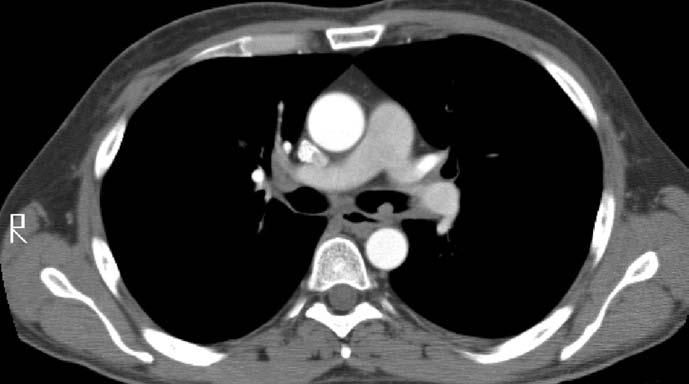

Laboratory evaluation revealed a normal complete blood cell count but mildly elevated levels of transaminases. A chest radiograph revealed a 2-cm cavitary right upper lobe (RUL) lesion (Figure 1). CT scans of the chest and abdomen revealed the solitary lung lesion, on a background of centrilobular emphysema (Figure 2), and bilateral non-homogeneous adrenal glands, with the left gland appearing larger than the right one (Figure 3). CT scans did not reveal any mediastinal lymphadenopathy or pleural effusions.

Figure 5 – This CT scan of the chest shows a polypoid endobronchial lesion in the left main-stem bronchus and a calcified periaortic lymph node (5-mm axial cuts, mediastinal window setting).

The patient was referred to otolaryngology for a biopsy of the mouth ulcers. The pathology of the left arytenoid and anterior subglottic region revealed ulcers with acute and chronic inflammation, reactive atypia, and yeast-like organisms. After the patient was referred to the oncology clinic with the presumptive diagnosis of metastatic cancer, CT scans revealed numerous small ring-enhancing cortical brain lesions (Figure 4) and a left main-stem endobronchial mass (Figure 5).